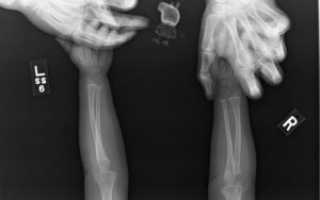

Особенностью рентгеновских лучей является их способность отображать на фотопленке внутреннюю структуру человека, что широко используется во многих отраслях медицины:

- Травматологии. Костная ткань менее прозрачна для электромагнитных лучей, именно поэтому кости отчетливо видны на рентгеновском снимке – это позволяет легко обнаружить любой дефект (трещину, перелом, воспалительный процесс).